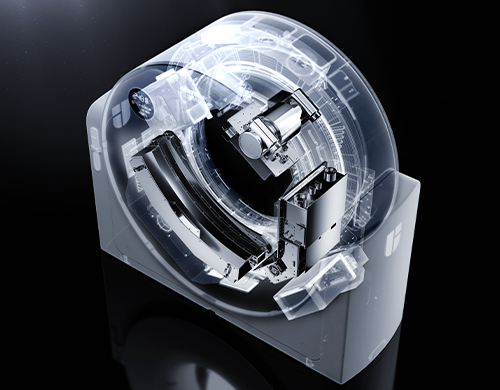

全面临床诊断分析应用

提供多种血管提取和中心线编辑工具,辅助诊断血管狭窄程度

支持结肠分割、中心线提取以及内窥图生成,高效获取结肠结构信息

多维度对肺部支气管、肺泡等实质结构进行量化评估与病变识别,帮助医生全面了解患者肺部健康状况

一键肺结节筛查可提升血管旁、磨玻璃等易漏结节识别效能,量化多维结节数据,助力肺病早筛早治

牙齿全景图、剖面图显示与神经通路标记,助力全面洞察齿科状况、科学制定齿科治疗方案

帮助快速识别并标记肋骨,一键实现肋骨平铺、展开、分割功能,提升骨科诊断效率